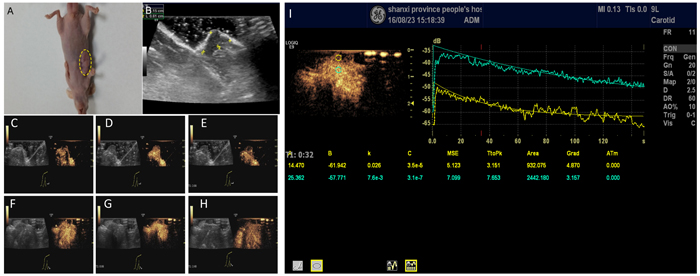

The inoculated H446 cells grew to a tumor of 1.0 cm after 4 weeks in 19 mice (Figure 5A, 5B). One mouse showed no xenograft tumor after 4 weeks. No animal died during the experiment. In vivo imaging of non-targeted and targeted NBs using the same experimental animal was done as internal-control with the same animal to reduce tumor heterogeneity and other experimental errors. Experimental program was to first observe the imaging effect of non-targeted NBs, then look at the imaging effect of targeting NBs. Since non-targeted NBs do not carry antibodies, there was no significant effect on blood circulation and tumor microenvironment in the experimental animals; and there was a 20-min intermittent period (wash period) which was sufficient for NBs to be completely cleared in vivo before injection of NBs. CDFI showed dotted blood flow signal in the xenograft tumor (Figure 5C, 5D) with targeted nanobubbles, but not with non-targeting nanobubbles (Figure 5F-5H).

CEUS with the targeted nanobubbles showed significantly higher peak intensity, area under the curve, and half-peak time in comparison with the blank nanobubbles (Table 1). There was no significant difference in time to arrival and time to peak between the targeted and the blank nanobubbles. Similarly, each parameter was significantly higher in tumor tissue compared to liver tissue (Figure 5I, Table 2), proving that the targeted nanobubbles penetrate the neovascular vessels of tumors and enter the tissue space.

Figure 5: Contrast-enhanced ultrasonography of xenograft tumor model. A profile of SCLC xenograft tumor (A) Measurement of the tumor size showed a diameter of 1.18 ± 0.12 cm (B, C-E) Early-stage of the contrast-enhanced ultrasonography of the tumor (C), peak intensity of the contrast-enhanced ultrasonography (D), and late-stage of contrast-enhanced ultrasonography (E) in targeting nanobubbles. Yellow dotted circles denote the tumor. Images in C, D, and E include B-mode and contrast images. (F-G) Same as C-E, except for in non-targeting blank nanobubbles. (I) Comparison of the time-intensity curves between the cancerous (yellow) and non-cancerous tissue (green).